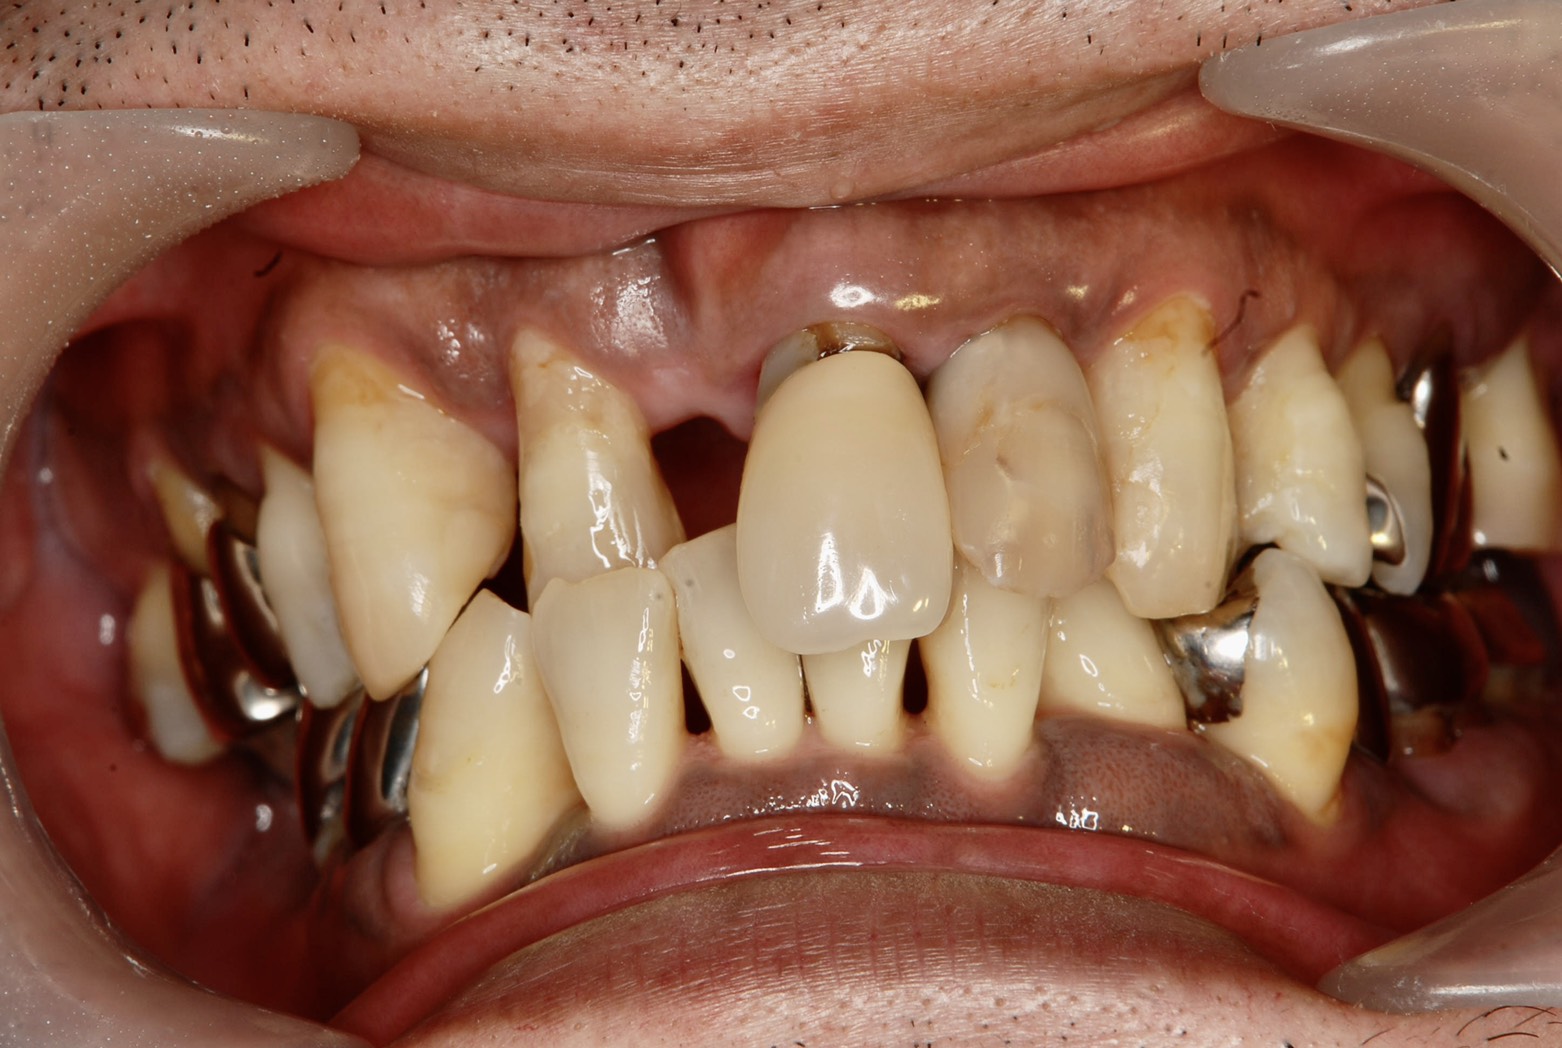

本日の患者さんは、右上前歯、1番が先天性欠損があり、審美改善の為にインプラント治療を希望されました。

2番を抜歯し2歯欠損になりますが、骨幅が狭過ぎて、1本しか埋入できないので、力の弱い2番ダミーのカンチレバータイプのプリッジになります。